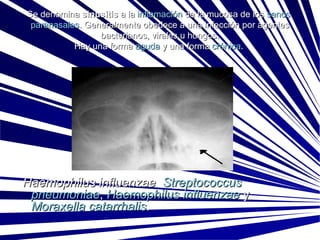

Se denomina  sinusitis  a la  inflamación  de la mucosa de los  senos   paranasales . Generalmente obedece a una infección por agentes bacterianos, virales u hongos. Hay una forma  aguda  y una forma  crónica .    Haemophilus influenzae    Streptococcus   pneumoniae ,  Haemophilus   influenzae  y  Moraxella   catarrhalis .